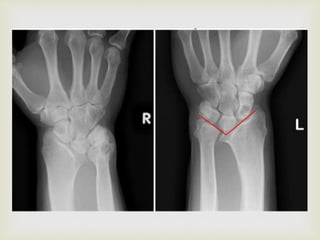

 The radius is curved, with its convexity dorsal and radial,

and there is a similar angulation of the distal radial

articular surface. The forearm is relatively short.

 The distal radial epiphysis is triangular because of the

failure of growth in the ulnar and volar aspects of the

physis; early closure of these aspects of the physis also is

frequent.

 The ulna is subluxated dorsally, the ulnar head is

enlarged, and the overall length of the ulna is decreased.

 The carpus appears to have subluxated ulnarward and

palmarward into the distal radioulnar joint, which

usually is spread apart.

 The carpus appears wedge shaped, with its apex proximal

within the lunate.

  The radiusis curved, with its convexity dorsal and radial, and there is a similar angulation of the distal radial articular surface. The forearm is relatively short.  The distal radial epiphysis is triangular because of the failure of growth in the ulnar and volar aspects of the physis; early closure of these aspects of the physis also is frequent.  The ulna is subluxated dorsally, the ulnar head is enlarged, and the overall length of the ulna is decreased.  The carpus appears to have subluxated ulnarward and palmarward into the distal radioulnar joint, which usually is spread apart.  The carpus appears wedge shaped, with its apex proximal within the lunate. Radiography